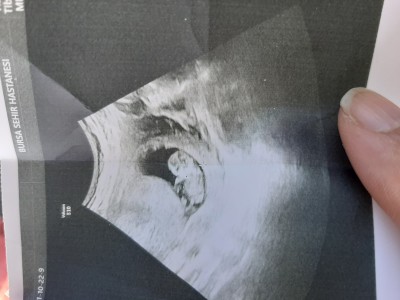

Kızlar 10+3 ultrason fotoğrafı tahmin var mi. Kese şekli ve nuba göre  erkek gibi hissettim. Doktor kız gibi  dedi net demedi ama. Ama ben baya baya erkek hissediyorum.  Rabbım sağlıkla nasip etsin.

Gebelik haftası 10+3